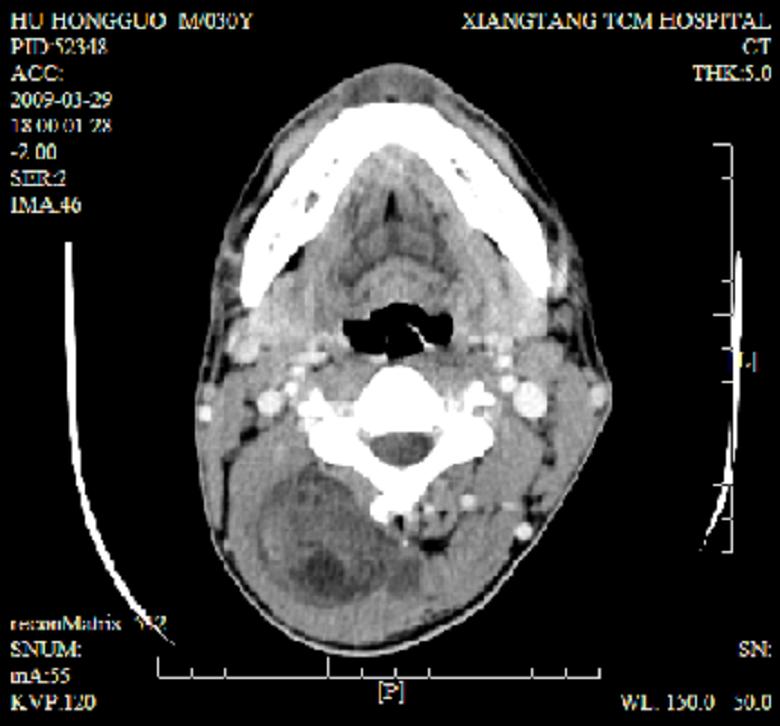

标题: CT19102:颈部肿块

男30y发现肿块3年

多处囊实性肿块,形态欠规则有一定形态,内见点状钙化,以囊变为主,增强后轻度强化,首先考虑神经源性肿瘤如鞘瘤,不除外脉管源性肿瘤如淋巴管瘤(见缝钻及囊性区域太多,如果合并感染完全可以这个影像表现),和海绵状血管瘤,但是血管瘤不太支持因为强化特征和病灶形态不典型.

右侧椎前间隙后部肌间、皮下囊性为主病变,可见分隔和点状钙化,分隔和壁呈轻度环形强化,大部分无强化。形态不规则,有钻缝特点。考虑1 淋巴管瘤合并感染2 血管平滑肌脂肪瘤3 表皮样囊肿4 不除外海绵状血管瘤。